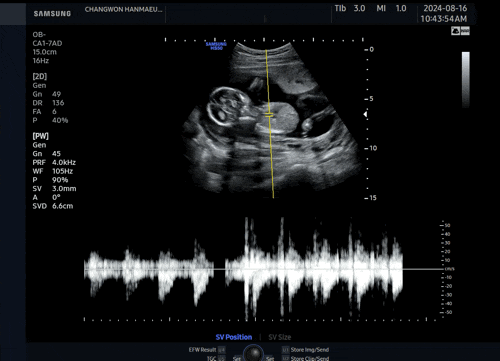

2024. 09. 13 (금) 8시 30분 채혈 9시 진료 예약 9시 05분 초음파실 진료 10시 교수님 진료 드디어 기다리...